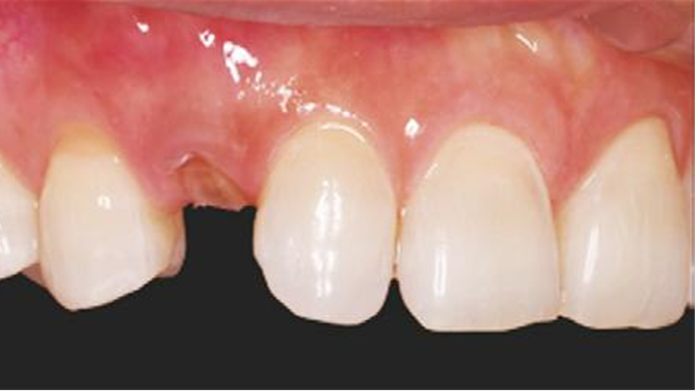

Clinical case: Patient-centered approach: treatment strategy for Root Membrane Technique & delayed implant placement

- Courtesy of Dr. Yoshiharu Hayashi, Japan -

Socket Shield Technique, anterior esthetics, maxillary anterior, esthetic, esthetics, delayed implant placement, socket preservation, AnyRidge, Root Membrane Kit, Root Membrane Technique, Partial Extraction Therapy, PET, esthetic zone, fuse abutment, Dr. Yoshiharu Hayashi,#11,#21,#22

AnyRidge implant system, fuse abutment Root membrane kit, PET Kit

“Advanced IntermezzoTM – one-piece solution for immediate placement & esthetic result in anterior region or narrow space.”